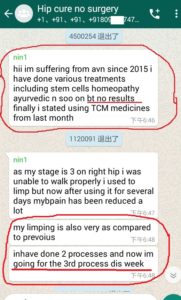

Following are some oversea patients recent feedback

Newly progresses(more will be uploaded soon)!

1. The Gentleman in Kenya started his treatment at his home April 27, now he said: (will update his more progresses soon)

3. The gentleman in India just started May, 2019. Actually he started on April 28, 2019 but he used it in wrong way and got less effects, ONLY on May 8, 2019 during our follow-up, we found his wrong-doing, and then corrected him. ONLY in 2 days, his pains significantly reduced!!!!